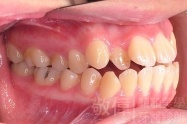

變臉矯正,原來戽斗妹跟大歪臉變成自信正妹

經由本院3D數影X光影像儀分析、與3D齒顎顏矯正技術,再配合口腔顎面正顎專科醫師施以正顎手術治療,雙方共同合作,使患者臉部外觀有很好的改善,大歪變小歪,產生了天南地北的大改變,她的人生也整個變得不一樣。

因為矯正與正顎手術的配合,使「戽斗妹」變成了「陽光正妹」,完全的改變了她的人生,在面對各種場合、與人交際都散發出自信微笑。所以,奉勸家長,如果小朋友有臉顎畸型的問題,應該考慮配合做這種簡單、安全、有效的正顎手術。